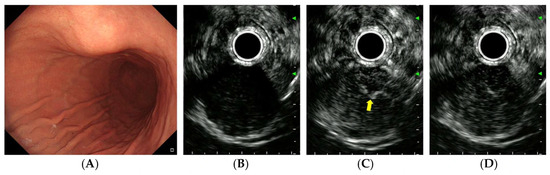

| CE-EUS findings | |||

| Arterial phase | |||

| Arterial enhancement | 0.024 | ||

| No/hypo-enhancement | 7 | 2 | |

| Iso/hyper-enhancement | 20 | 39 | |

| Irregular vessels | 0.017 | ||

| Absent | 21 | 20 | |

| Present | 6 | 21 | |

| Venous phase | |||

| Diffuse enhancement | 0.035 | ||

| Absent | 9 | 5 | |

| Present | 18 | 36 |